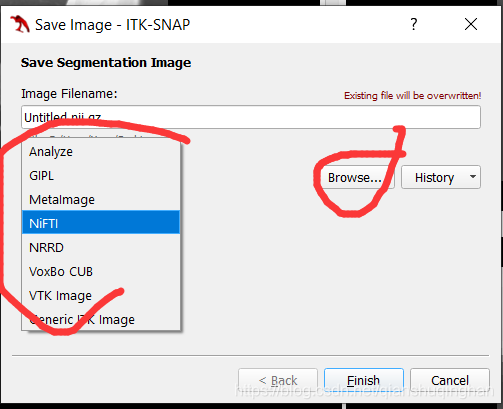

可选为标注结果的文件类型和保存位置